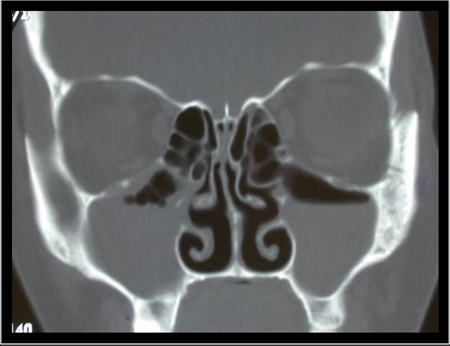

nasal endoscopy

Recommended in selected patients (e.g., patient refractory to empirical antibiotic therapy, concern for antibiotic resistance, patient immunocompromised) as it can provide excellent visualisation of the nasal cavity and sinuses.

[Figure caption and citation for the preceding image starts]: Nasal endoscopy of the left nasal cavity showing a small polyp and pus in the middle meatusFrom the collection of Joseph K. Han [Citation ends].

mucosal erythema, purulent discharge